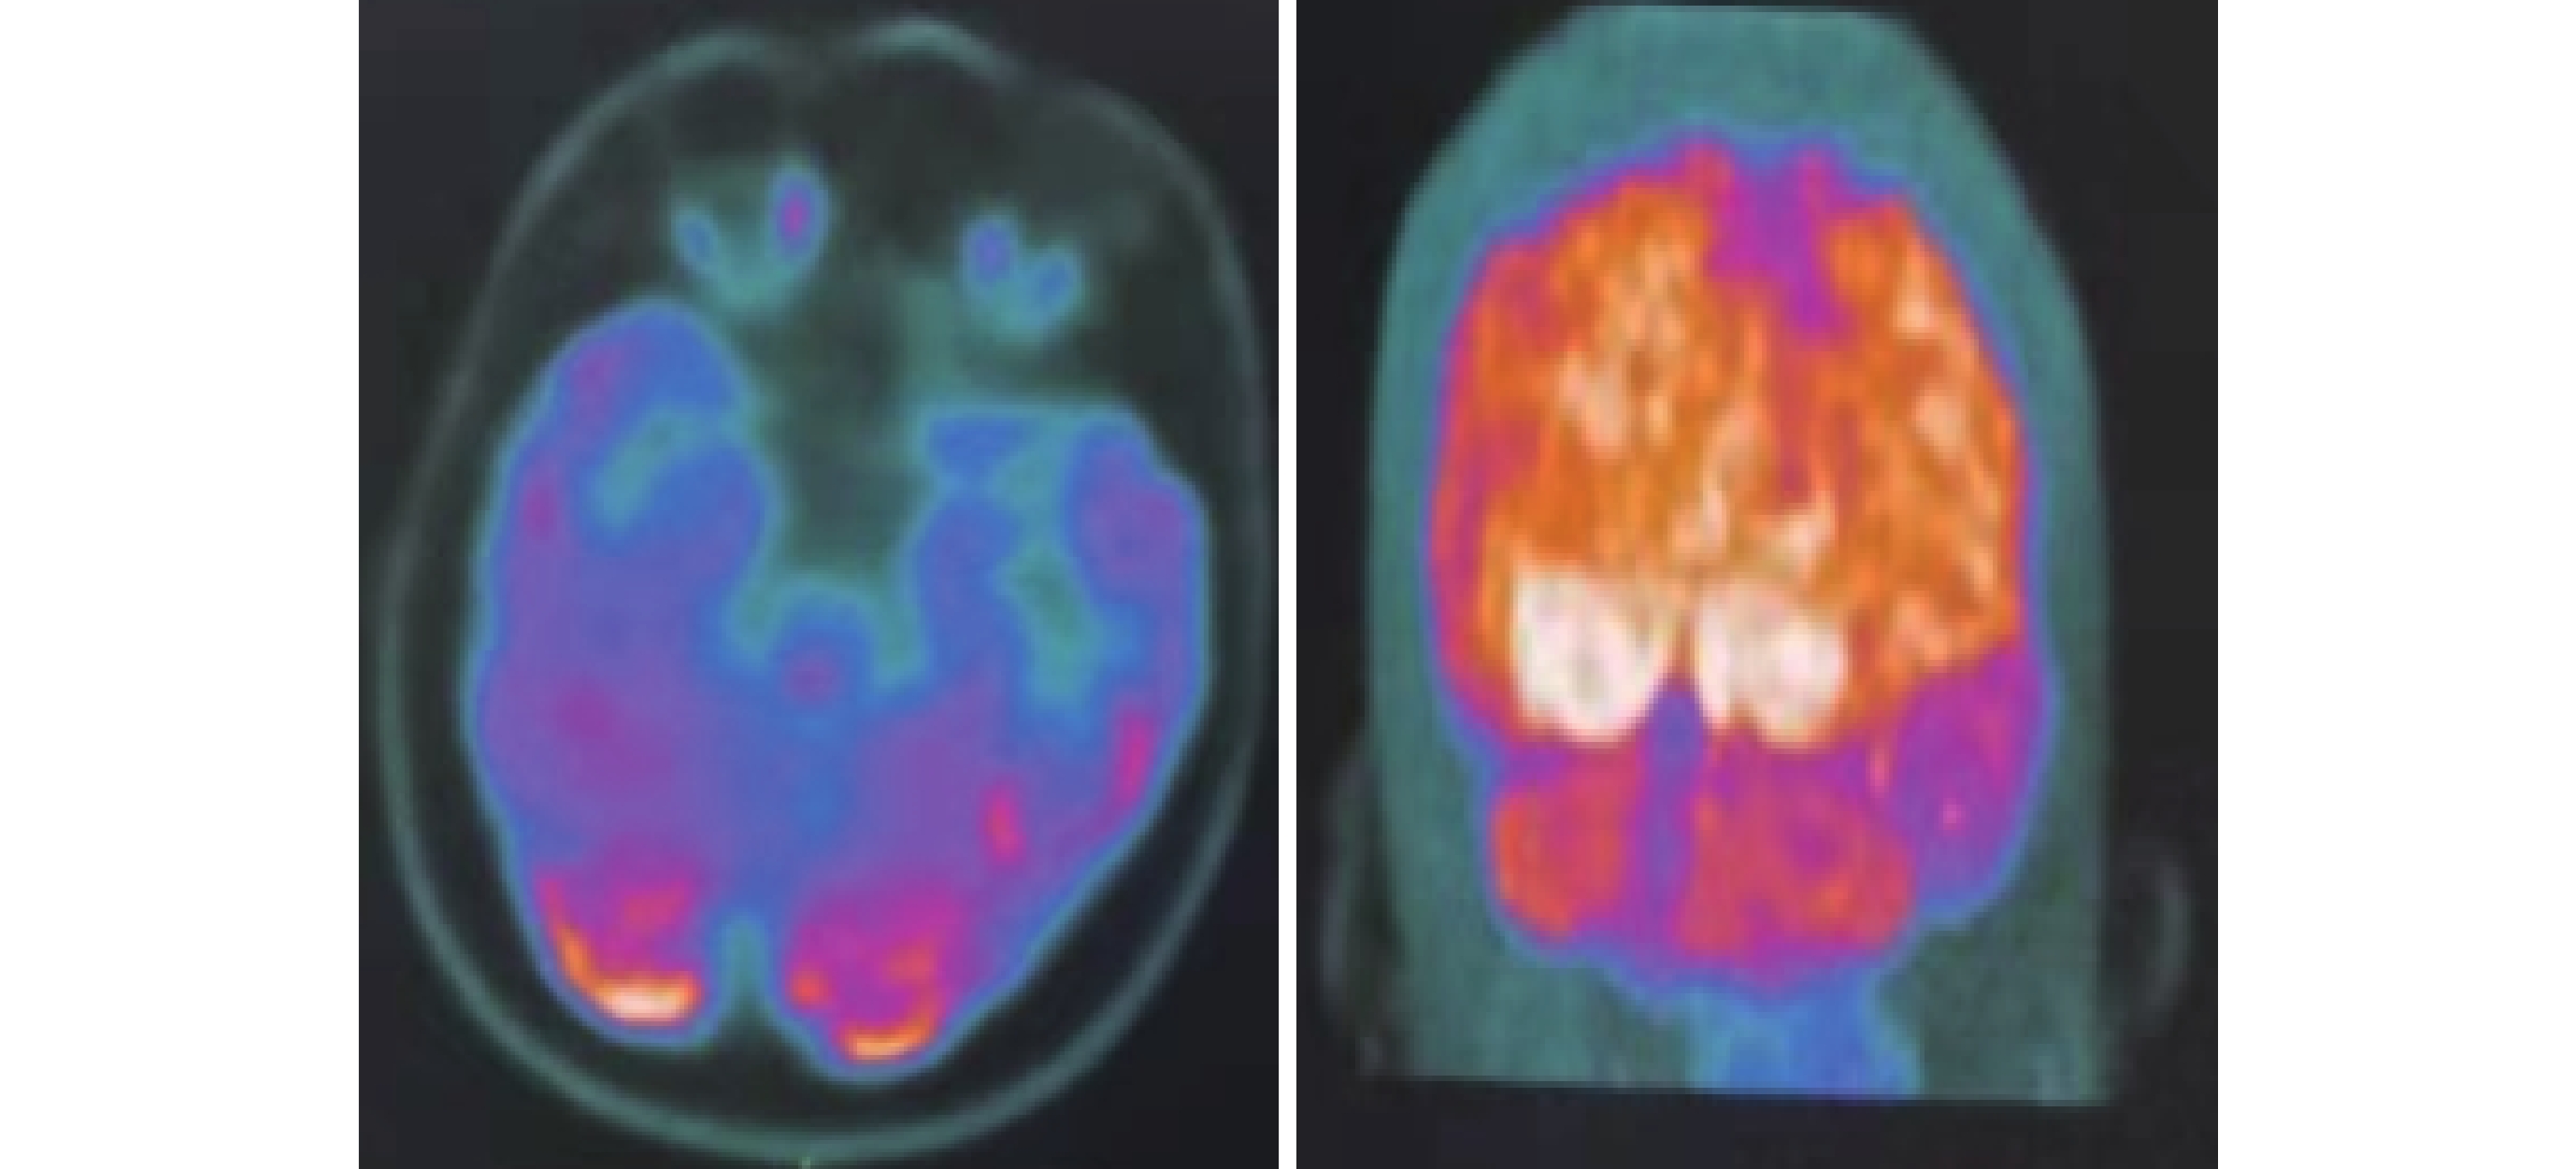

影像學檢查:17歲時,頭部計算機斷層掃描(Computed tomography,CT)示:顱內多發對稱性鈣化灶、左側腦回高密度影(圖1)。18 歲時,頭部磁共振成像(Magnetic resonance imaging,MRI)平掃及彌散加權成像+癲癇特殊序列示:顱內多發缺血變性灶、左側海馬較對側萎縮可考慮 、雙側上頜竇及蝶竇炎透明間腔形成。正電子發射計算機斷層顯像(Positron emission tomography,PET)示:雙側額葉近中線處代謝減低,左側顯著;雙側顳葉代謝減低,左側顯著;左側海馬較對側萎縮,無異常代謝減低;雙側丘腦、雙側基底節區、雙側皮髓質交界區多發對稱性鈣化灶以及透明間腔擴大(圖2)。